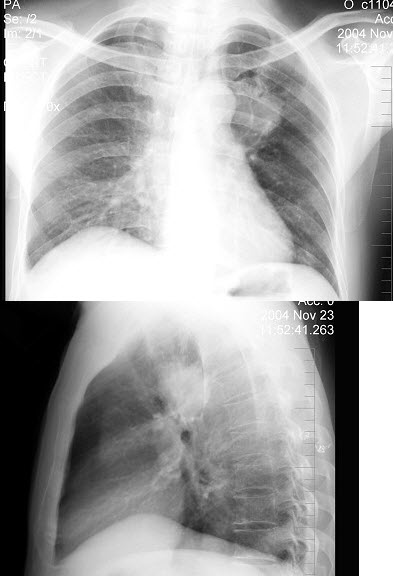

A.粘膜皱襞迂曲

男,54岁,咳嗽咳痰,胸痛,痰中带血丝,近2月明显,消廋乏力,有吸烟史30余年,胸片如图,最可能的诊断是()

A.左肺结核瘤

B.肺转移瘤

C.炎性假瘤

D.原发性肺癌

E.结节病